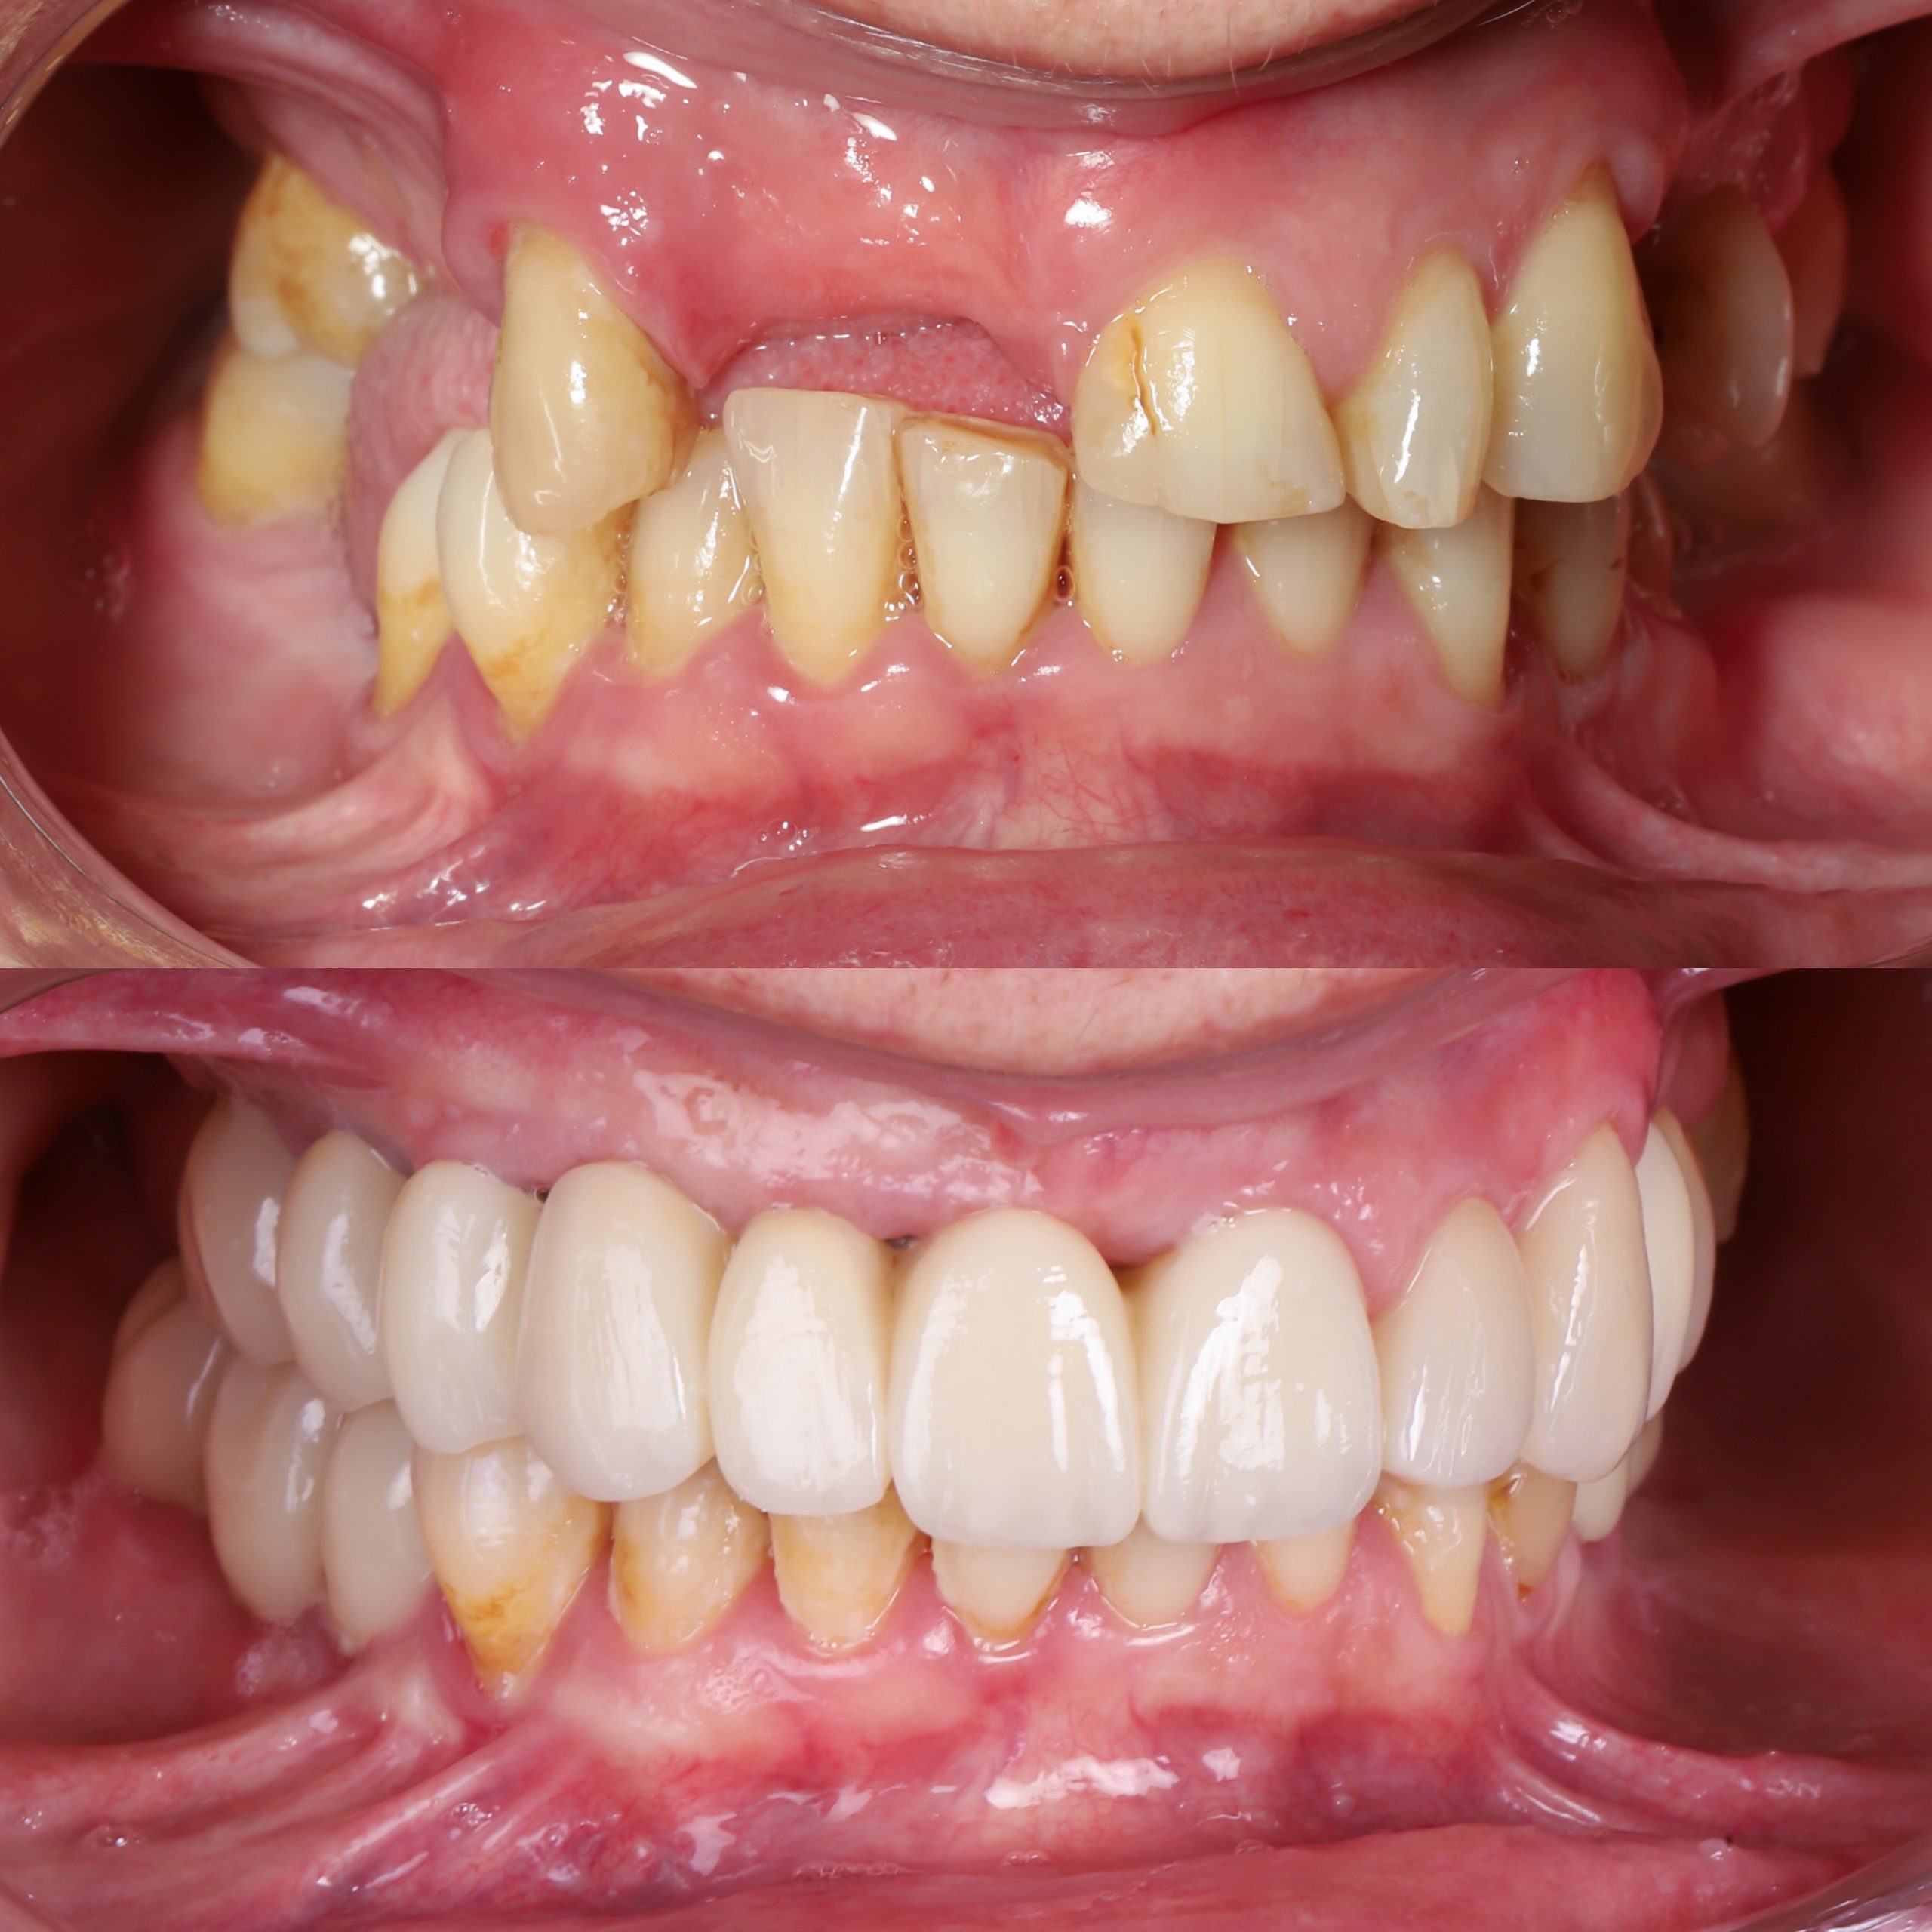

fotos Antes y después

En esta secciones te enseñamos decenas de casos de antes y después de colocación de implantes dentales y carillas de alta estética